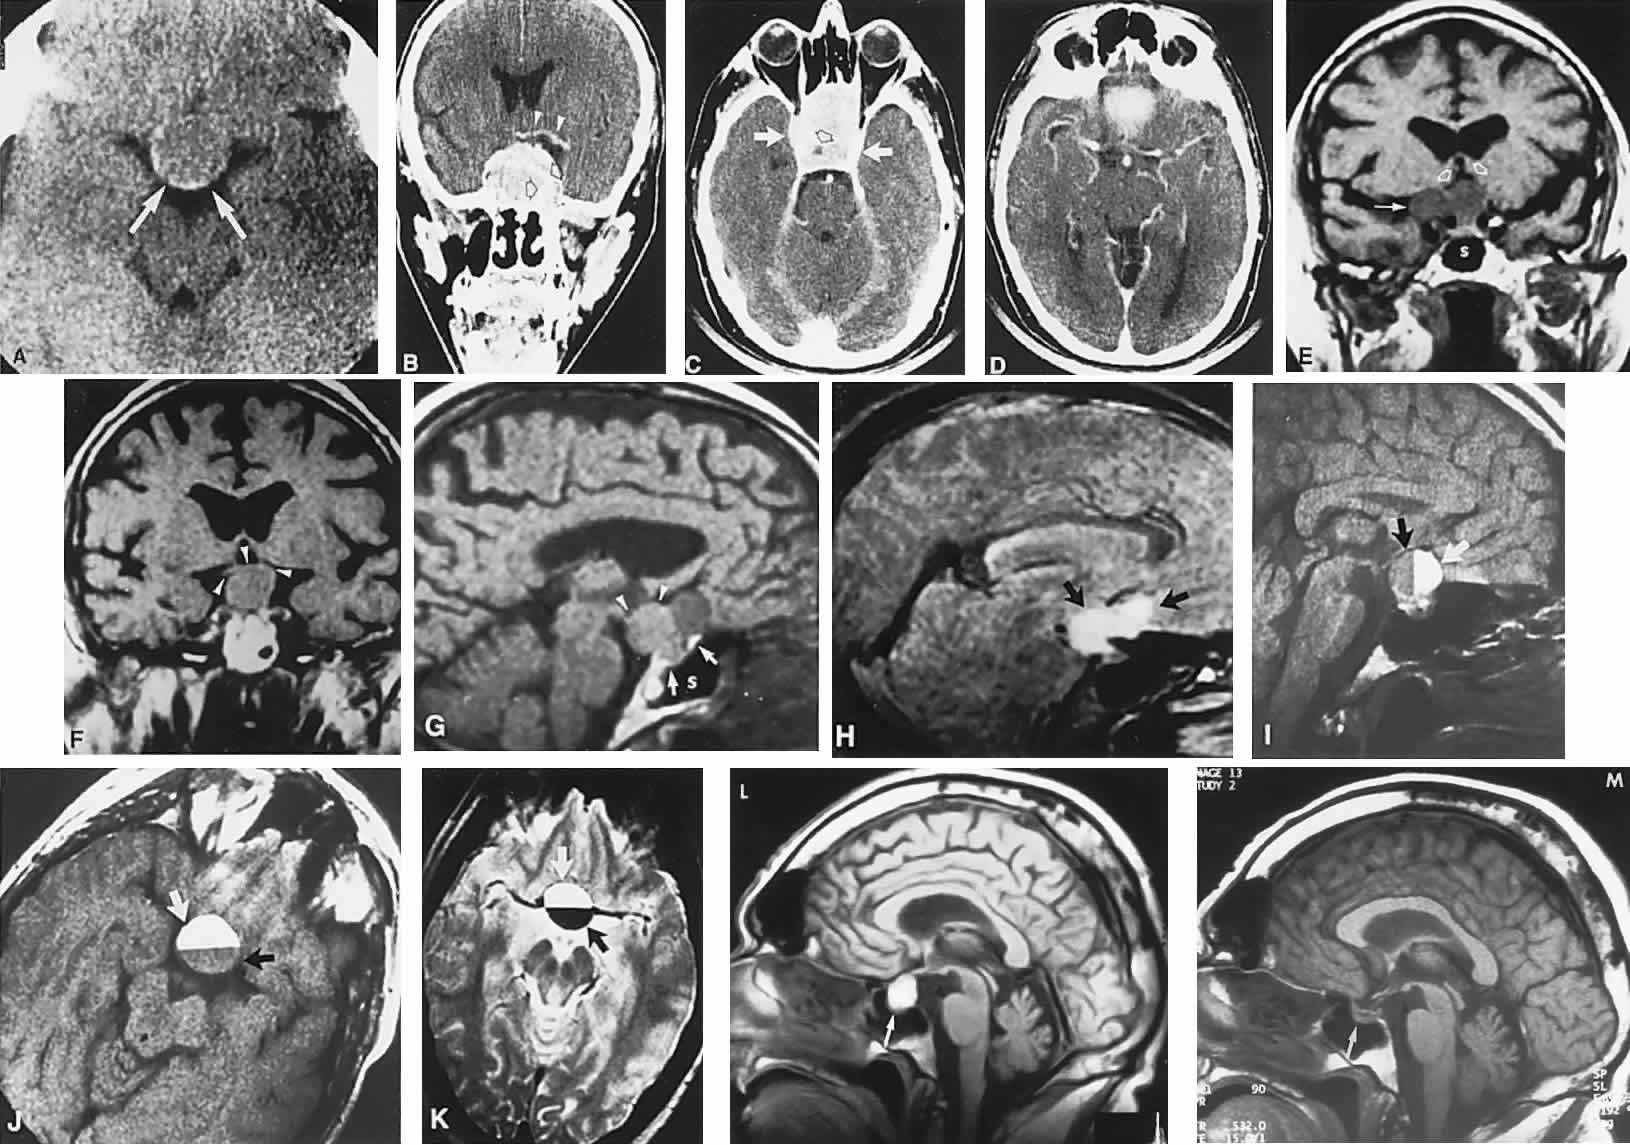

Fig. 2. Large prolactinoma. Original vision in the right eye (RE) was 8/200, left eye (LE) 1/200, with serum prolactin of 26,000 ng/ml and galactorrhea. Four months of bromocriptine reduced prolactin to 661 ng/ml, vision improved to RE 20/40, LE 20/50. At 3 years, vision was as follows: RE 20/30, LE 20/20; prolactin was 25.9 ng/ml. Enhanced magnetic resonance imaging. Sagittal (A) and coronal (C) images at diagnosis. Sagittal (B) and coronal (D) images at 2-year follow-up, showing dramatic shrinkage of the mass.

With the advent of the ergot-derived dopamine agonist bromocriptine, there is a pharmacologic alternative (or adjunct) to surgery for prolactinomas. Bromocriptine (2-bromo-alpha-ergocryptine) is representative of a class of ergot derivatives that, since the early 1970s, have been known to inhibit pituitary gonadotropic function, reduce PRL secretion, and diminish the size of pituitary tumors (see Fig. 2). Such ergot derivatives are structurally related to dopamine, a PRL-inhibitory factor elaborated by hypothalamic dopaminergic neurons. It is likely that bromocriptine acts in two ways: dopamine turnover in tubero-infundibular neurons is depressed, thereby increasing hypothalamic dopamine; dopamine receptors of the pituitary are inhibited, reducing both spontaneous PRL secretion and the release of PRL provoked by thyrotropin-releasing hormone. At any rate, bromocriptine decreases PRL production and secretion, with resultant reduction in lactotrope size and subsequent diminution of tumor volume, often rapidly, within 1 to 2 hours of initiation of treatment.25